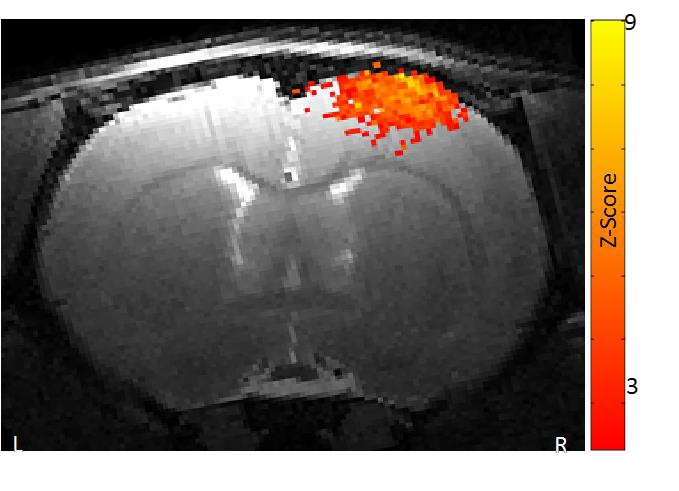

2、功能磁共振成像

功能磁共振成像需要最強(qiáng)的磁場(chǎng),最好的梯度和最穩(wěn)定的系統(tǒng)。布魯克優(yōu)異的梯度系統(tǒng)確保在單次激發(fā)下得到整個(gè)腦部的圖像。功能卓越的勻場(chǎng)單元最大程度地消除平面回波成像幾何形變。特有的頻率和相位穩(wěn)定性保證多次激發(fā)EPI擴(kuò)散張量成像的品質(zhì)。高分辨率的功能磁共振成像可以深入洞察大腦的功能反應(yīng)。

小鼠腦部的功能磁共振成像: